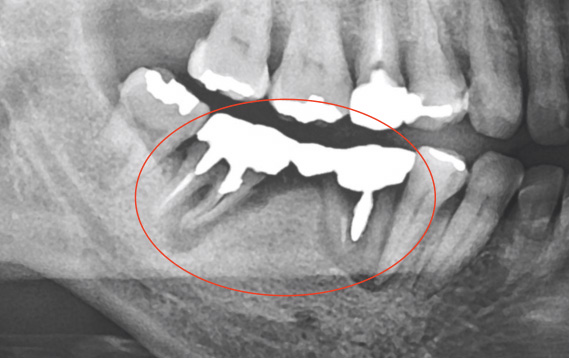

ただし、むし歯の進行の深さと、歯髄の炎症の程度は比例するとは限りません。なぜなら、歯髄には細菌の進行を防ぐ防御機能が備わっているからです。特に大人のむし歯でゆっくり進行したものは、「むし歯が大きいのに痛くない」といったことも起こりえます。

したがって、レントゲンによる判断だけではなく、種々の検査を総合的に判断してからの治療になります。

歯髄温存療法の適応は歯髄の炎症が「ない」もしくは「部分的」なものに限られます。

感染を起こしたままでもしばらくは無症状に経過するものの、時間が経ってから、根尖性歯周炎という形で現れ、再治療が必要となることがありますが、その時の治療の成功率はだいたい5割と言われております。